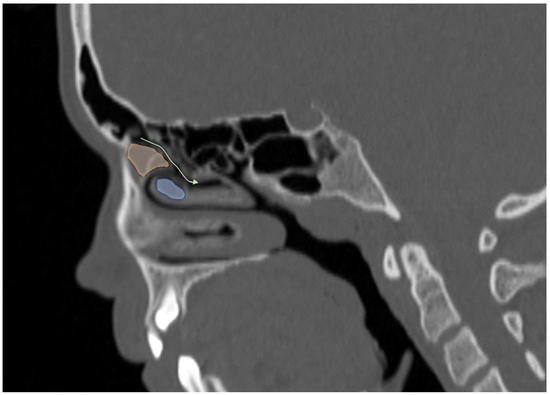

Comparison of Two Methods for Assessing the Maxillary Sinus Volume in Patients with and Without Unilateral Cleft Lip and Palate: A Retrospective Cross-Sectional Study

Background/Objectives: The aim of this study was to compare two methods for maxillary sinus volume measurement, assessing their accuracy. The analysis compared the maxillary sinus volume in patients with unilateral cleft lip and palate (UCLP) and in a non-cleft group, using a manual method and a three-dimensional (3D) semi-automated segmentation method. Methods: The research was conducted according to the STROBE guidelines. Sixty patients were included in this study: thirty patients with UCLP were in the research group, and the control group consisted of 30 patients with no craniofacial deformities. Cone-beam computed tomography (CBCT) was analyzed. The manual maxillary sinus volume was calculated based on its approximation to two geometric shapes based on mathematical formulas using linear measurements that were performed on all sinus CBCT scans in the maximum diameter in three planes. The semi-automatic segmentation method using ITK-SNAP 3D-imaging software version 4.2.2 was used to automatically calculate the maxillary sinus volume of the sinuses. The manually calculated volume was compared with the automatically calculated one, and statistical analysis was performed. Results: The cleft group presented lower values in both the automatic and manually calculated volumes for both the right (automatic: p = 0.49; manual p = 0.009) and left (automatic: p = 0.46; manual p = 0.11) maxillary sinuses than the non-cleft group. The cleft group presented statistically significant higher discrepancies in values between the manual and semi-automatic method than the control group (RMSV p = 0.0011; LMSV p = 0.033; TMSV p = 0.003). Conclusions: The manual method may not reveal the exact anatomical topography of the maxillary sinuses. In UCLP patients, the maxillary sinus anatomy may be more complex. Therefore, a semi-automated method may be more advisable to preserve the accuracy of the measurements. Full article

Show Figures

Figure 1